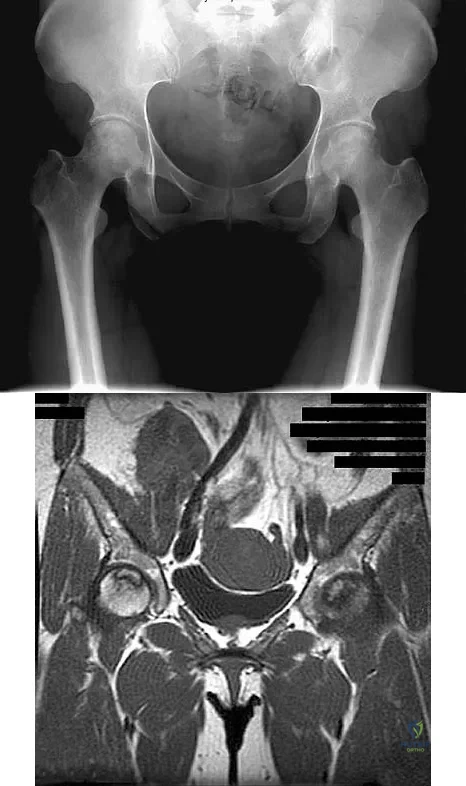

Figures 61a and 61b show the CT and MRI scans of a 40-year-old man who has hip pain. He undergoes total hip arthroplasty and curettage and cementation of the lesion as shown in Figure 61c. Histopathologic photomicrographs of the curettage specimen are shown in Figures 61d and 61e. What is the best course of treatment?

Explanation